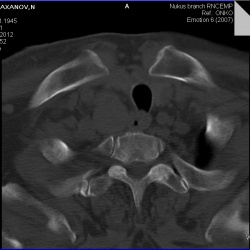

Можно ли отнести изменения в С2 к кистовидным просветлениям при спондилезе?